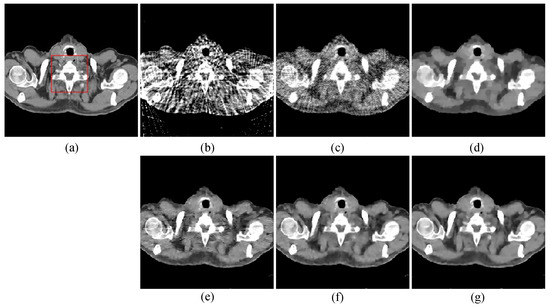

To compare the recovery of reconstructed image details and edge information, we selected two regions of interest (ROIs) from the 48-view and 64-view reconstructed images and zoomed in to show. The ROIs are labelled with red box as shown in Figure 2a and Figure 3a. The corresponding zoomed-in results are shown in Figure 5. As can be seen from the figure, our algorithm can reconstruct some small image structures shown by the arrows, which are difficult to see by other algorithms. Also, we find that our algorithm performs better in edge retention.

Figure 5. The ROIs from 48-views and 64-views reconstruction results. The first row is from 48-views ROI. The second row is from 64-views ROI. (a) ground truth, (b) FBP, (c) OS-SART, (d) TV, (e) PICCS, (f) TVPI-G, and (g) NPICCS. The display window is [−150 250] HU.